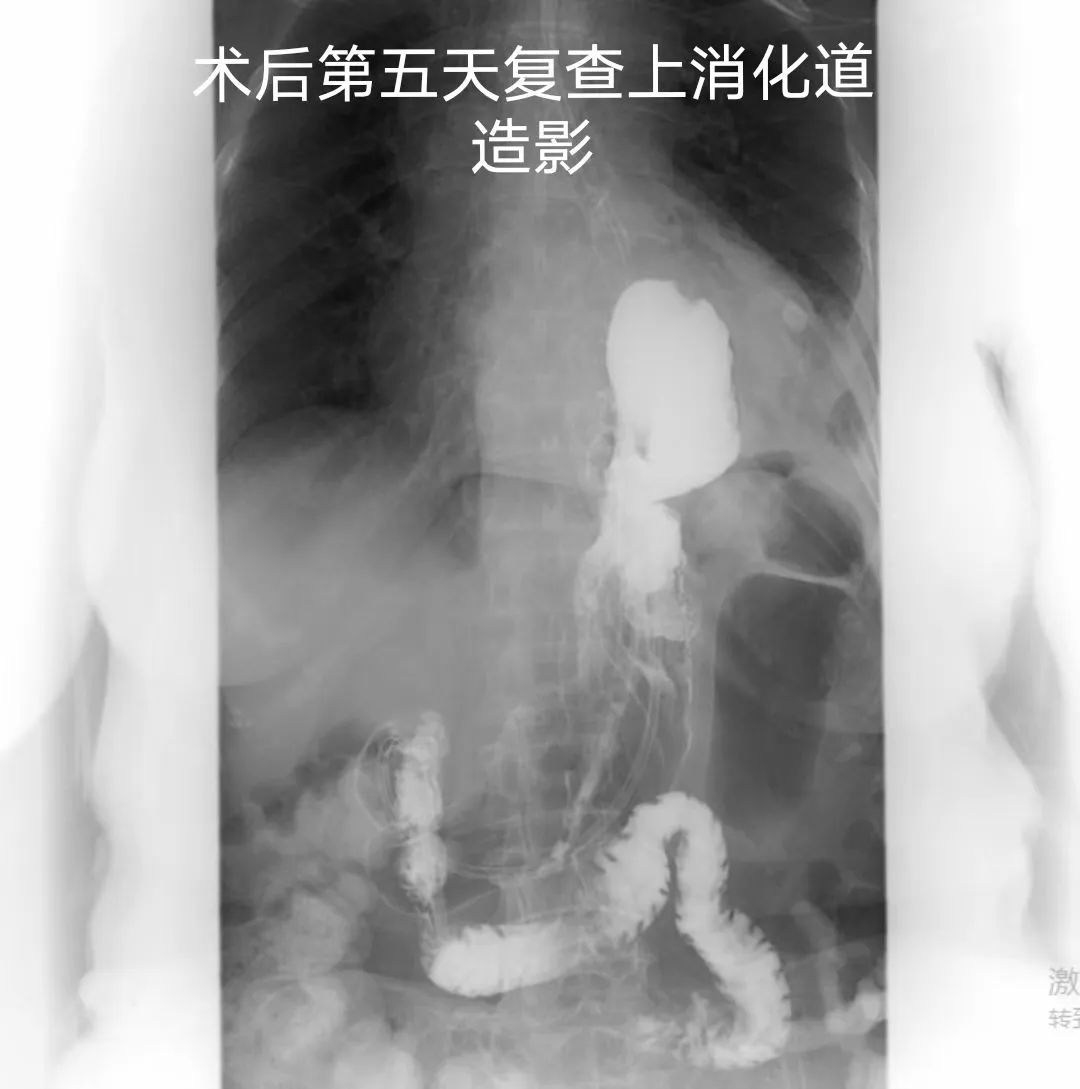

术后科室医护团队密切监护老人的病情变化,悉心治疗护理,尽力把每个细节做到最好,患者及家属亦积极配合。经过医患共同努力,术后5天复查上消化道造影提示吻合口及胃排空良好,术后7天经口进食,术后10天顺利出院,老人及家属喜悦之情溢于言表。